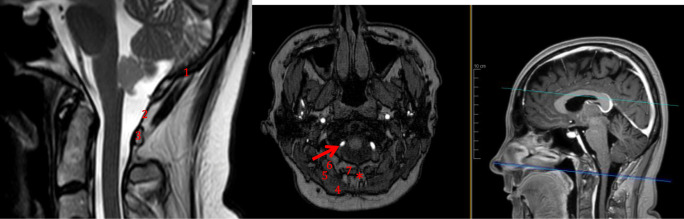

Relevant surgical anatomy

The anatomy of the fourth ventricle and its surroundings is shown in Fig. 1. The specific surgical anatomy is shown in Fig. 2. The midline skin incision starts 2 to 3 cm below the external occipital protuberance and should extend circa 4 cm inferiorly. Attention should be paid to stay on the midline, i.e., into the nuchal ligament, since it is an avascular plane. Image intensifier control or navigation may be used to avoid unnecessary detachment of the posterior spinal muscles [1–6].

Fig. 1.

Relevant anatomy of the 4th ventricle and its surroundings. 1, fourth ventricle; 2, foramen Magendie (median aperture); 3, aqueductus sylvii; 4, cerebellum (arbor vitae); 5, pons; 6, cisterna magna; 7, planum occipital ossis occipitalis; 8, atlanto-occipital membrane; 9, posterior arch of C1; 10, obex

Fig. 2.

Relevant surgical anatomy of the minimally invasive sub-occipital approach. 1, lower aspect of the occipital bone; 2, atlanto-occipital membrane; 3, posterior arch of C1; 4, M. trapezius; 5, M. semispinalis capitis; 6, M. rectus capitis posterior major; 7, M. rectus capitis posterior minor; asterisk, nuchal ligament (avascular plane). Red arrow, extradural segment of the vertebral artery (V3)

The vertebral artery turns around the lateral mass of the atlas from lateral to medial and enters into the foramen magnum through the atlanto-occipital membrane. The midline of the atlanto-occipital membrane has to be identified before the foramen magnum is carefully drilled. After opening the dura, the cisterna magna is seen. The foramen Magendie and obex are identified, in between the two cerebellar tonsils. The distal floor of the fourth ventricle may be seen (Fig. 3).